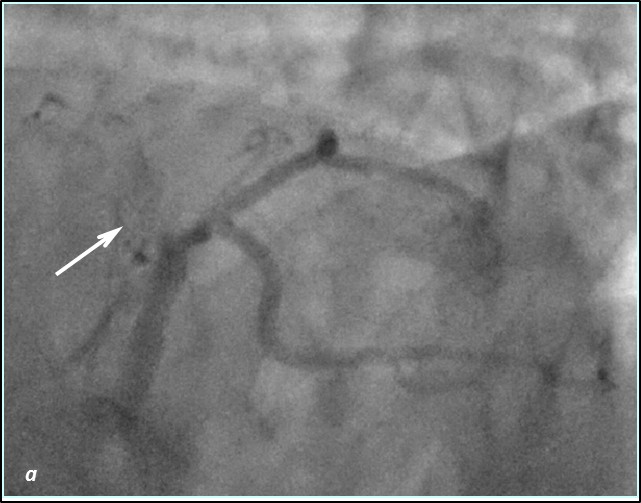

До проведения реваскуляризации миокарда пациент получал двойную антиагрегантную терапию (клопидогрел 75 мг, ацетилсалициловая кислота - 300 мг ежедневно). Чрескожное коронарное вмешательство было разделено на два этапа. Первым этапом – планировалось выполнить реканализацию и стентирование ПМЖВ, вторым – стентирование ПКА. Однако по данным повторной коронарографии было выявлено сужение тела ствола левой коронарной артерии (ЛКА) на 30%, окклюзия от устья передней межжелудочковой артерии (ПМЖВ), постокклюзионный сегмент заполнялся по слабым внутри- и межсистемным коллатералям, устьевое сужение огибающей артерии (ОВ) 60%, окклюзия средней трети правой коронарной артерии (ПКА), постокклюзионный сегмент заполнялся по внутрисистемным перетокам. Показатель Syntax Score для данного пациента составил 34.5. Учитывая, что по данным ранее выполненной коронарографии, правая коронарная артерия оставалась проходимой, а передняя межжелудочковая ветвь была окклюзирована и на момент реваскуляризации срок окклюзии составлял 7 лет, была проведена сменена тактики и первым этапом выполнена реканализация правой коронарной артерии, а спустя 2 суток – реканализация и стентирование передней межжелудочковой ветви от устья с баллонной ангиопластикой огибающей ветви (рис.1,2). Учитывая, что проводилась реканализация хронической окклюзии, в обе коронарные артерии были имплантированы стенты с лекарственным покрытием Resolute ONYX (Medtronic).

Рис.2 Ангиограмма левой коронарной артерии. а) при коронарографии левой коронарной артерии –артерия окклюзирована от устья (стрелка); б) проходимость по левой коронарной артерии полностью восстановлена